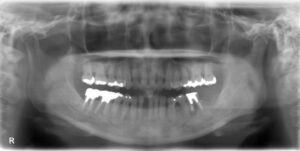

下顎臼歯5本欠損症例

BEFORE AFTER 61歳女性/下5本欠損/インプラント埋込手術 【治療内容】 右下は第一小臼歯と第一大臼歯を繋ぐ…